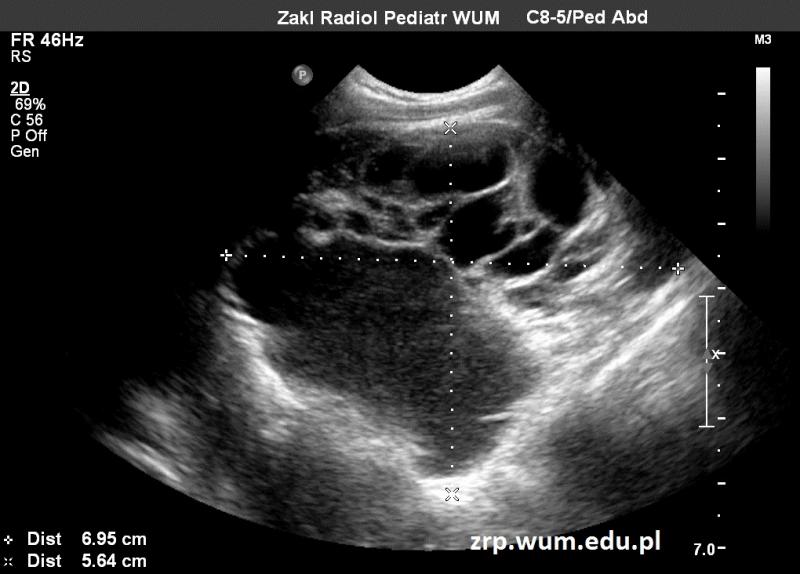

Przypadek 34: 5-letni chłopiec po złamaniu obojczyka prawego. Po zdjęciu gipsu w badaniu przedmiotowym wyczuwalny guz/torbiel w okolicy dołu podobojczykowego prawego.

Rozpoznanie: Kontrolne RTG nie wykazało zmian. W badaniu USG uwidoczniono wielokomorową zmianę torbielowatą, z przegrodami, o łącznych wymiarach ok.70x56x55mm; zmiana widoczna w dole pachowym prawym, sięga przedniej okolicy barkowej. Dwufazowa zawartość niektórych z komór zmiany.

Obraz USG odpowiada naczyniakowi limfatycznemu. Zmiana najpewniej była obecna już wcześniej, uległa powiększeniu po urazie.